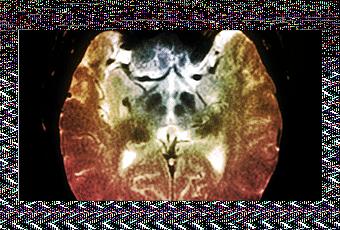

Los autores del estudio sometieron a un nuevo test de habilidades cognitivas a estos participantes, ahora con edades comprendidas entre los 63 y los 65 años. Asimismo, escanearon sus cerebros utilizando una técnica de neuroimagen denominada morfometría basada en voxels (VBM) para determinar los volúmenes de materia gris y blanca ubicados en las áreas frontales y en el cerebelo de estas personas .El hallazgo más interesante de este estudio es que el volumen de materia gris del cerebelo permite predecir la inteligencia general de un individuo. Sin embargo, los resultados son diferentes en hombres y en mujeres, pues en los hombres se ha demostrado la existencia de una relación más fuerte entre el volumen del cerebelo y la inteligencia general.

Se sabe que el cerebelo está implicado en las funciones sensorial-motoras, entre las que se incluye el equilibrio y el ritmo de los movimientos. Sin embargo, ahora se comienza a intuir que el cerebelo también juega un papel clave en las habilidades cognitivas de mayor nivel.Según el primer autor de este trabajo, Michael Hogan, la inteligencia general está correlacionada con diversos aspectos básicos de la eficiencia en el procesamiento de la información que, dependen del funcionamiento del cerebelo, incluidas la velocidad y la consistencia de la percepción y decisiones y la rapidez con la que podemos aprender nuevas habilidades. Esta es una prometedora investigación, que sugiere que podría haber una puerta trasera para lograr el mantenimiento de las funciones corticales mayores en las personas de mas edad, a través de la activación sostenida de las redes del cerebelo mediante actividades sensorial-motoras y cognitivas, que según los autores, el cerebelo busca para regular y automatizar, trabajando en colaboración con el córtex.